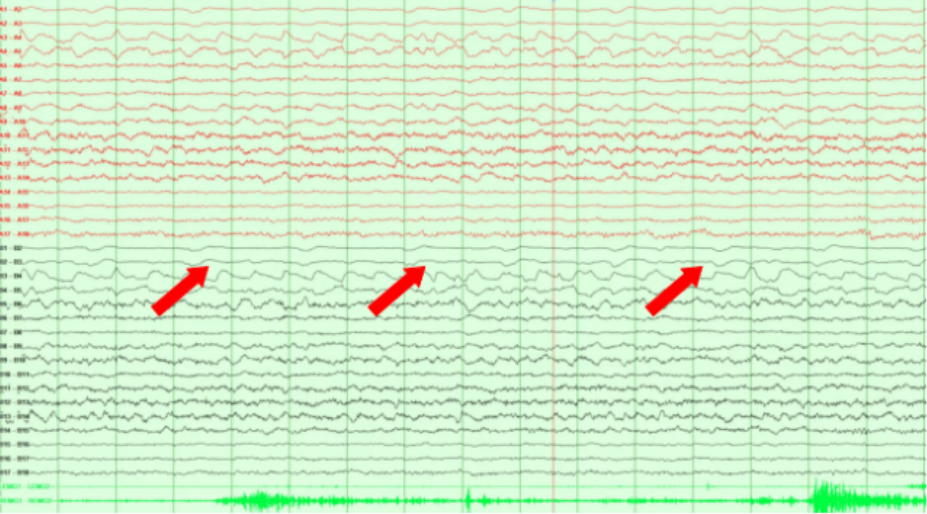

毁损后SEEG监测结果未见异常放电

相比于传统的开颅手术创口大、恢复慢、易损伤周围神经结构,这是一种全新的手术方式,SEEG热凝毁损的优势就是安全精准、微创和效果。术后小文的癫痫未再发作,且脑电图提示既往HFO消失,复查影像效果理想,机器人引导立体定向脑电图技术在热凝毁损错构瘤技术上优势显著。